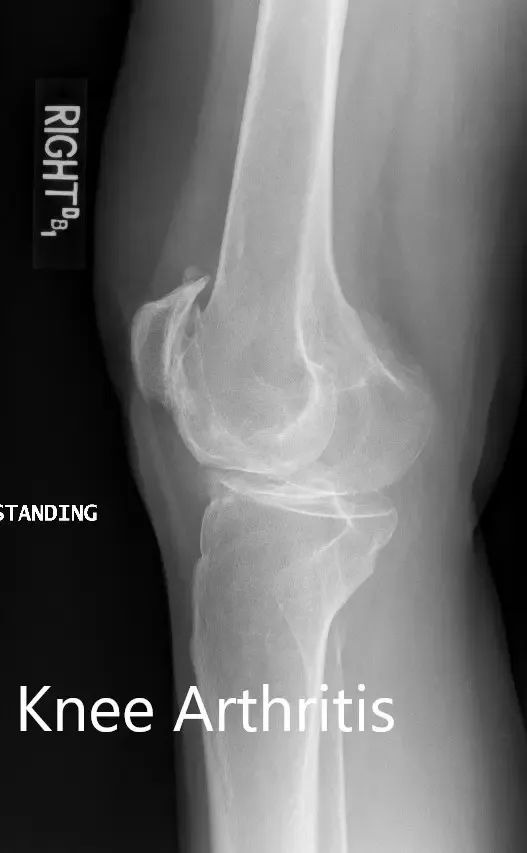

Los estudios de imagen realizados revelaron osteoartritis tricompartmental severa en ambas rodillas. Teniendo en cuenta que su estilo de vida limitaba el dolor de rodilla y el agotamiento de opciones conservadoras de manejo, le recomendaron un reemplazo bilateral de rodilla. Se le consideró candidato para un reemplazo total de rodilla personalizado. Él estuvo de acuerdo con el plan.

Radiografía preoperatoria que muestra las vistas laterales de la rodilla derecha e izquierda respectivamente